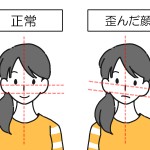

顔が歪んでいるのは歯並びのせい?歯列矯正で改善することはあるの?